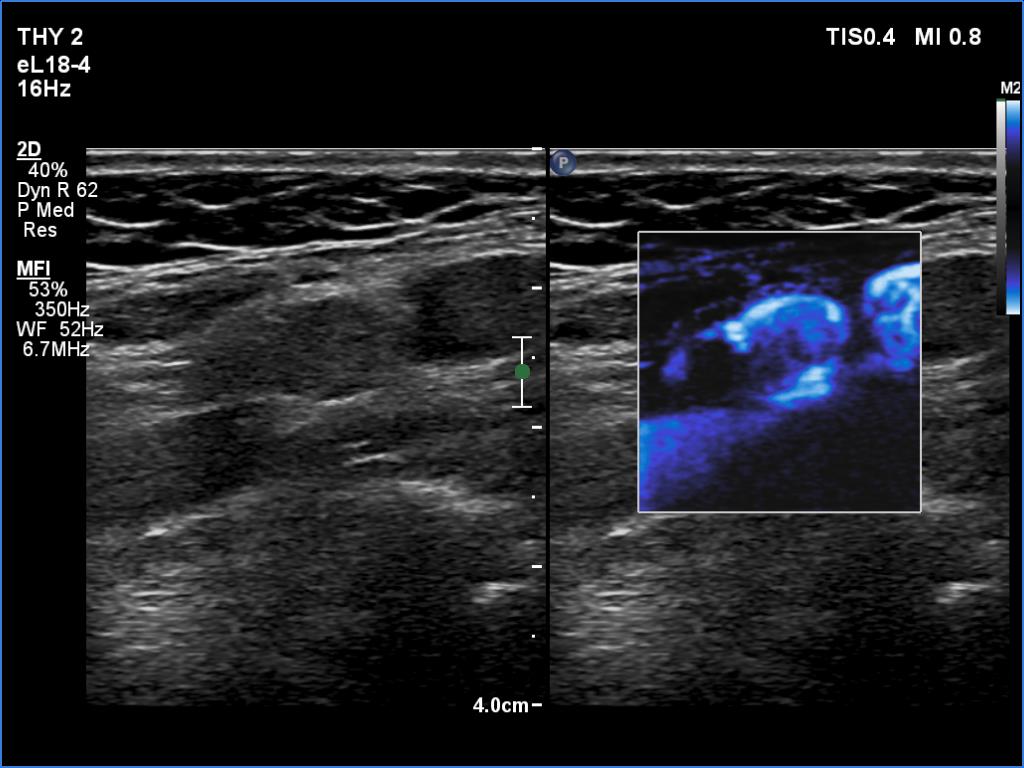

Lymph nodes - case conp 090

18 months after surgery (ultrasonographic picture 10)

Left side of the neck, another longitudinal scan, microflow imaging. Vessels running at the periphery of the lymph node are predominant.